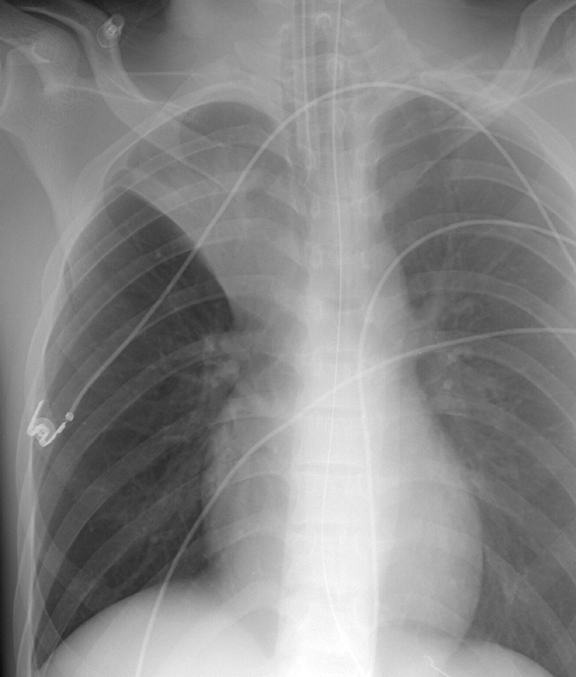

Gallery Lobar Collapse RUL Collapse RUL Collapse Case 6 PA only

RUL Collapse Case 6 PA only